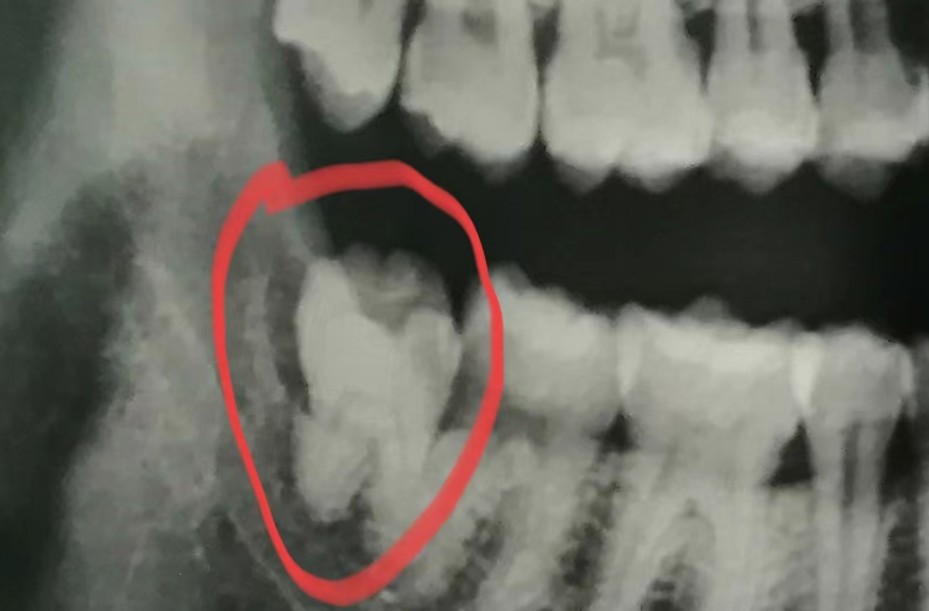

智齿的位置还是长得比较正的,本来没打算拔掉了,结果最近又发炎疼痛,索性长痛不如短痛。

今天拔的是右下的智齿,约800元,感觉都好贵。